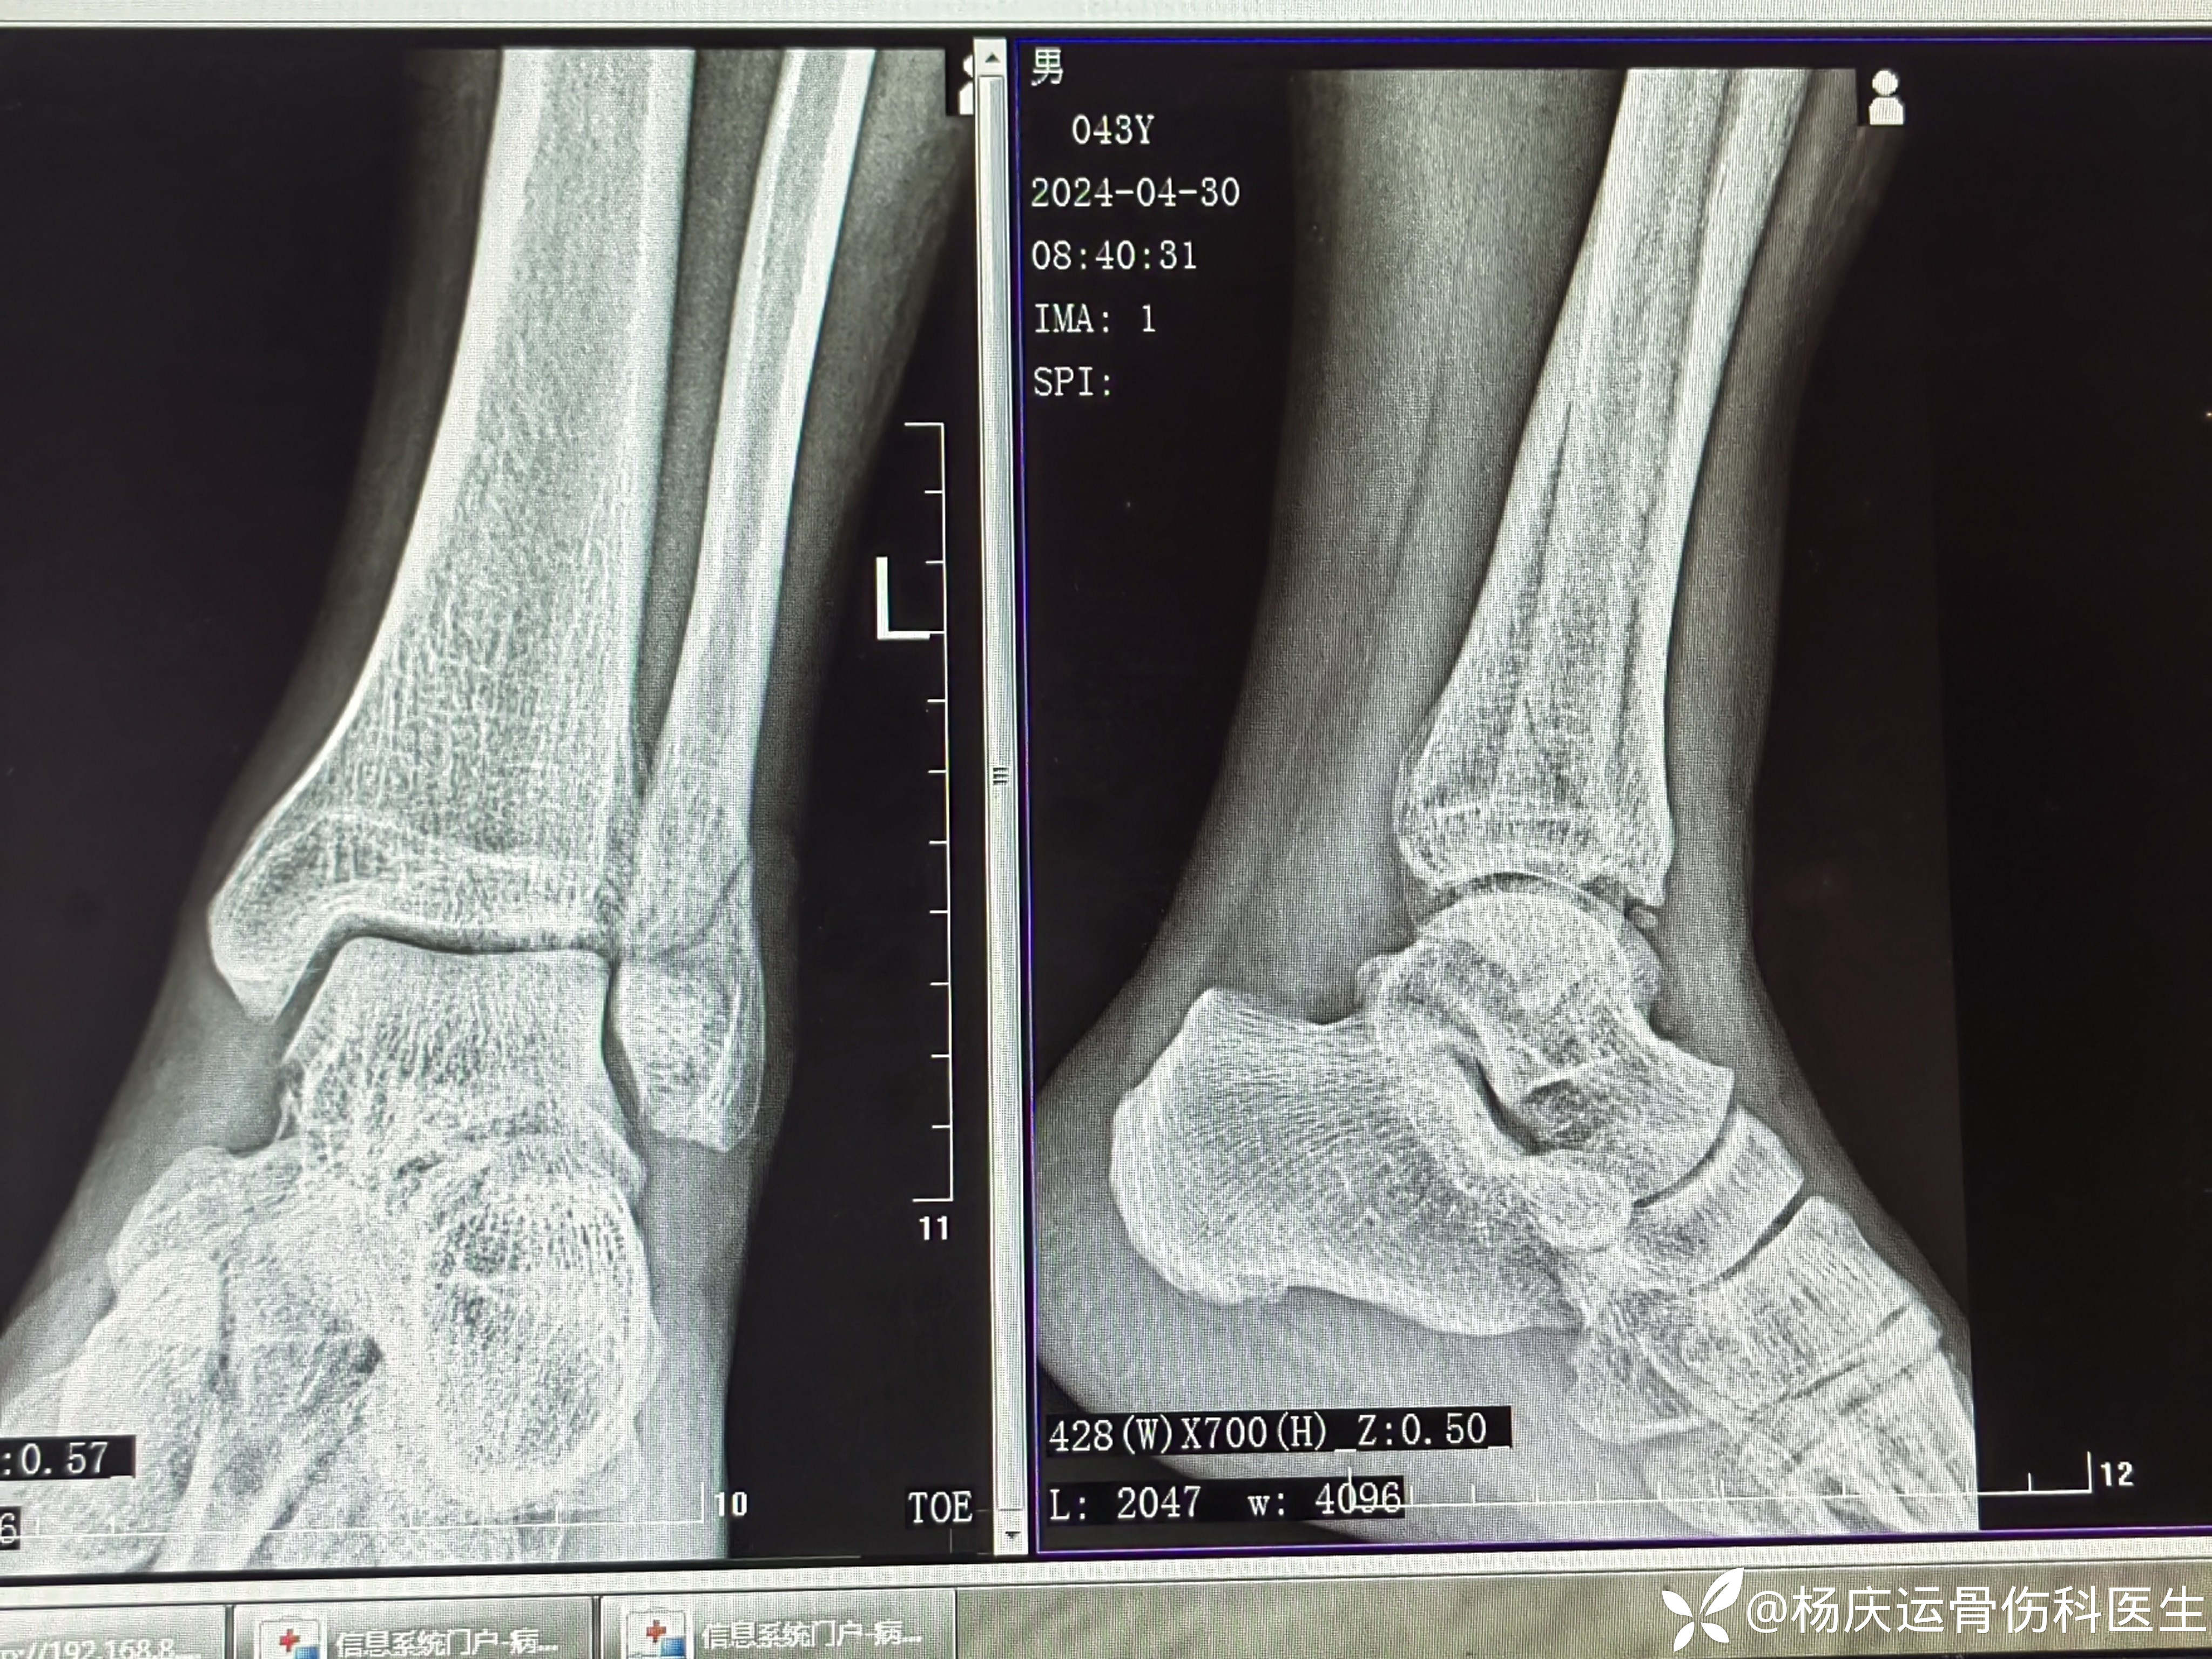

3周复查

5周复查